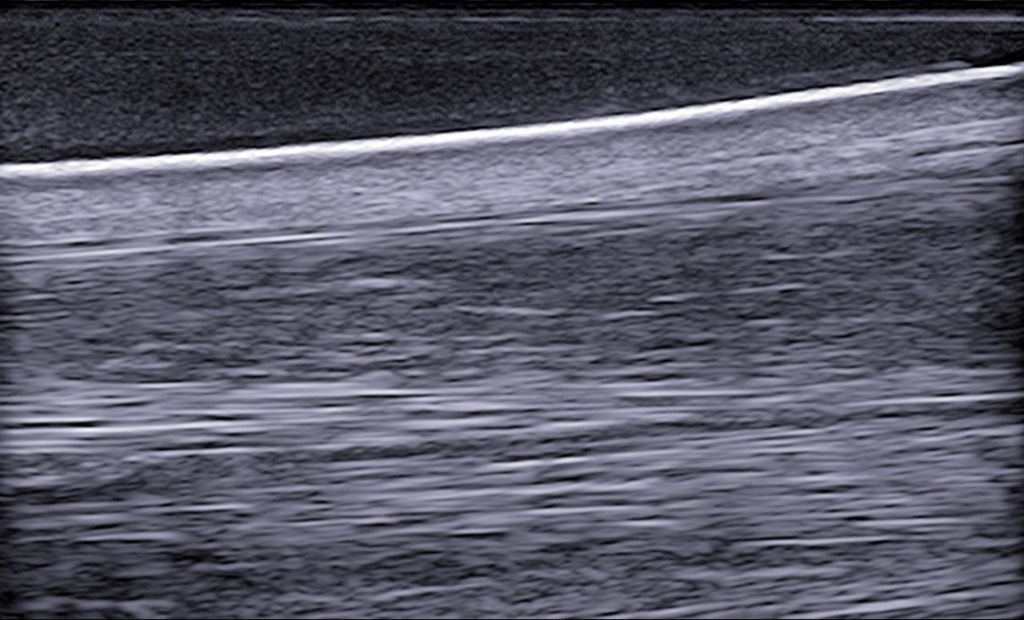

De zachte weefsel laten de geluidsgolven goed door, daardoor zijn deze goed te beoordelen door middel van echografisch onderzoek. Pezen en banden bestaan uit lange vezels en zullen zich meestal aftekenen als duidelijk omlijnde structuren met daarin heel veel kleine vezeltjes. Op de scan zien we de vezeltjes als kleine puntjes als we de pezen in dwarsdoorsnede scannen of lange lijntjes als we ze in de lengte scannen.

Een peesblessure kan op verschillende manieren tonen bij een peesscan. Meestal is er bij een grote recente blessure sprake van zwelling rondom de pees en is de pees zelf ook toegenomen in omvang. Met name blessures in het hart van de pees zijn vaak zichtbaar als een donkere holte in het midden van de pees. Als we een beschadigde pees in de lengte richting bekijken dan valt op dat er een donkere strook, zonder vezelbanen, in de pees aanwezig is.